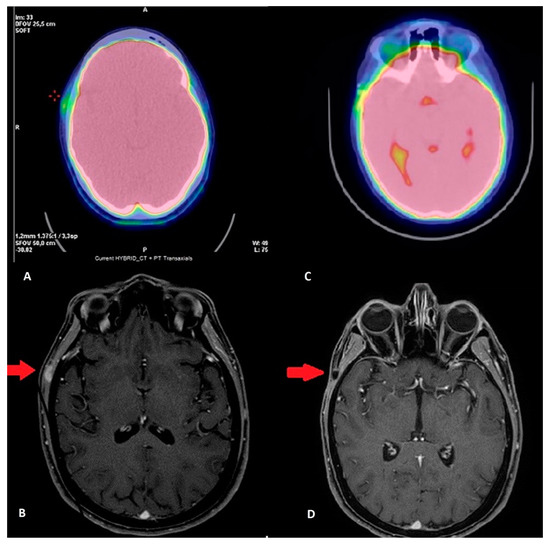

Case Description

3. Results